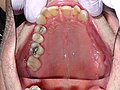

A ce niveau, des microfibres musculaires provenant du muscle buccinateur vont s'étendre sur le conduit parotidien et agir sur l'ouverture de la lumière ductale [4]. Il se termine en s'ouvrant obliquement dans la cavité buccale en regard du collet de la première ou deuxième molaire supérieure.

Le canal s'abouche dans la cavité buccale par un orifice au sommet d'un petit relief de la muqueuse de la joue : la "papille du conduit parotidien". Il se situe donc médialement à la branche descendante de la mandibule.

Schéma anatomique représentant le trajet du canal parotidien- Position des papilles parotidiennes, en regard du collet des deuxièmes molaires supérieures.